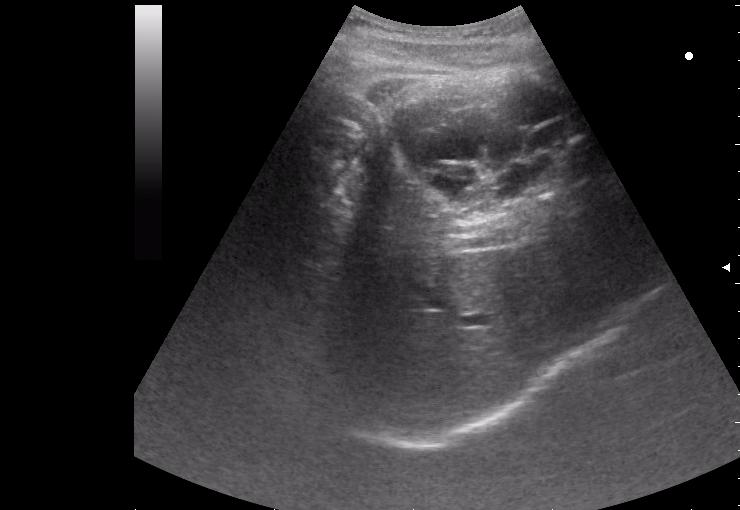

нагноение остаточной полости